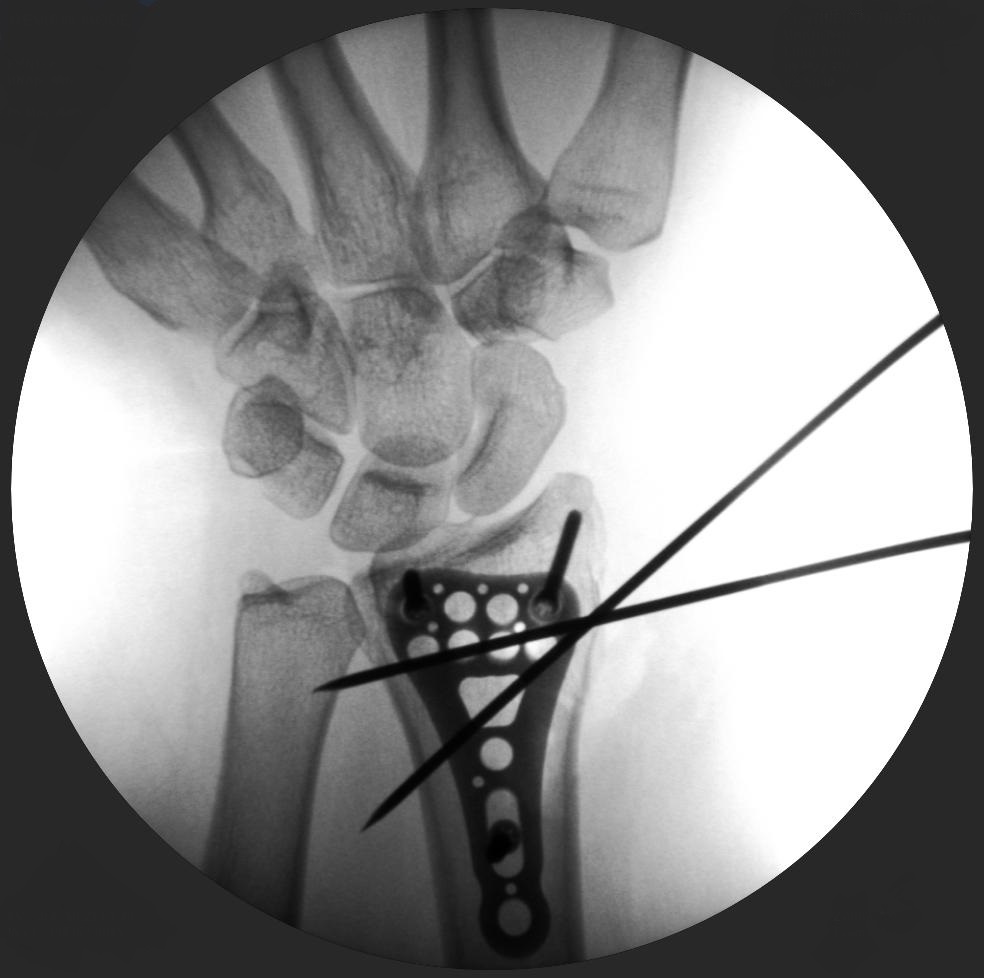

Skan-C plays a critical role in orthopaedic procedures, providing excellent imaging during interventional procedures, and allowing for precise localization and accurate treatment. The ability of Skan-C to offer dynamic visualization of visualization structures enhances patient safety, minimizes complications, and improves the overall effectiveness of orthopedic interventions.

CRIF - Closed reduction internal fixation

ORIF - Open reduction internal fixation

High-quality imaging

Skan-C uses advanced imaging technology, such as pulsed fluoroscopy and digital subtraction angiography, to provide highly detailed images of the affected area. This allows doctors to perform procedures with increased precision and accuracy, and better patient outcome